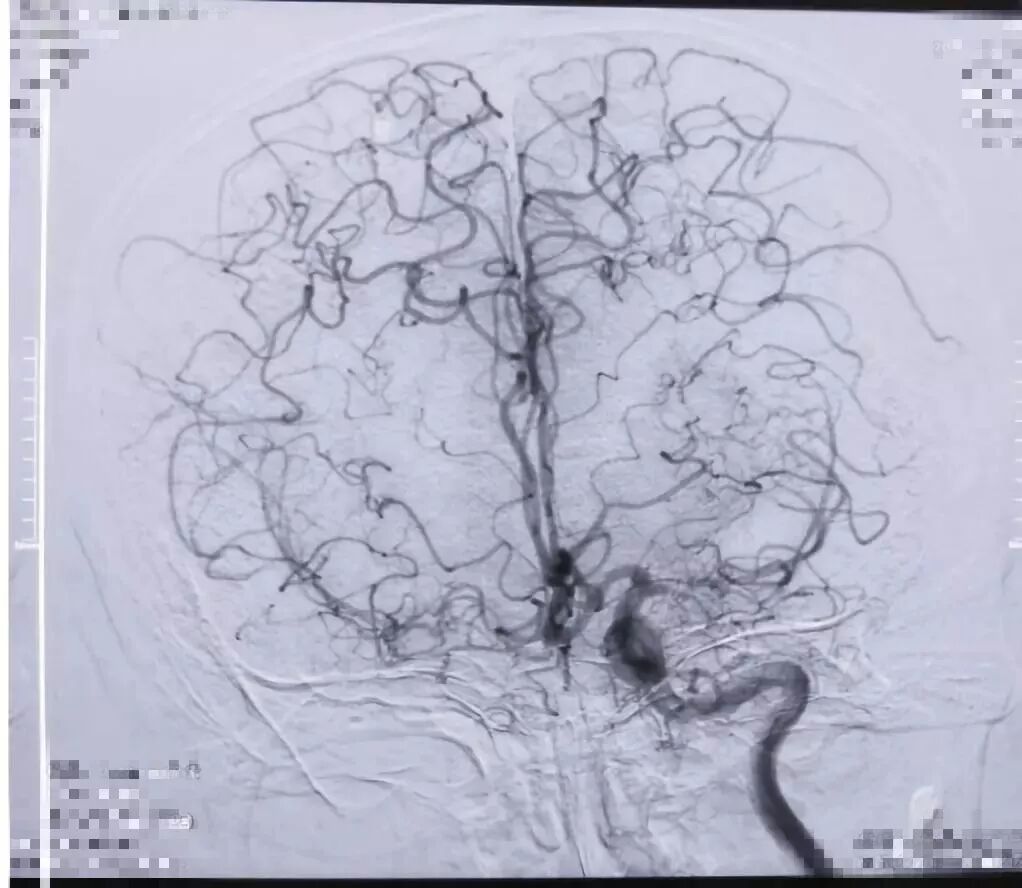

术中造影

术后半年(10月)入院复查DSA,示吻合口通畅,并行左侧脑血管重建术(STA-MCA吻合+颞肌贴敷术)